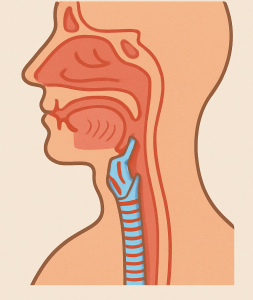

Επεμβάσεις στοματικής κοιλότητας / Φάρυγγα

Αμυγδαλεκτομή, αδενοτομή, μορφώματα βάσης γλώσσας …